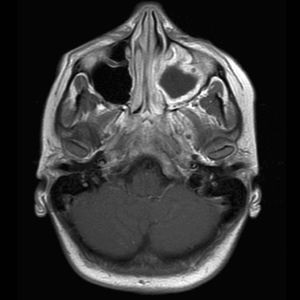

Egy felmérés szerint az MRI elsősorban tanulni a nyálkahártyával. Annak érdekében, hogy értékelje a daganat kialakulásában, polyposis, és azt is, hogy milyen mértékben sorvadás a köpeny, az orvos irányítja a beteget az MRI vizsgálat. Hatékony az ilyen típusú leképezés olyan esetekben, amikor azt végzik annak érdekében, hogy vizsgálja meg a labirintus, és ék üregek. A magatartási kiküszöböli gombás sinusitis, érzékeli a gyulladásos betegségek és komplikációk merültek fel a koponyán belül, és azonosítani rosszindulatú daganatok.